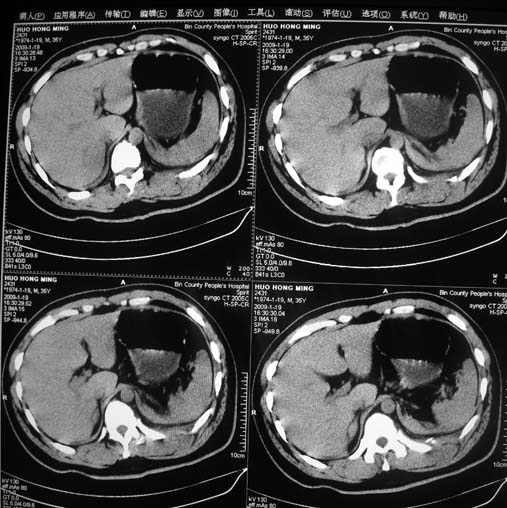

以下是引用余辉在2009-1-20 8:22:00的发言:[br]右侧肾上腺明显增大、边缘不光整,肯定有问题,结合患者病史考虑肾上腺挫伤、伴血肿形成。[br]另左肾后唇包膜下方可见局限性新月形高密度影,考虑肾包膜下出血[br]余同意楼上,建议增强排除脾破列

以下是引用随光逐影在2009-1-20 8:21:00的发言:[br]1)左侧多发肋骨及部分腰椎左侧横突骨折。2)左侧肾旁后间隙及同侧胸腔积血。3)左侧腰大肌肿胀。